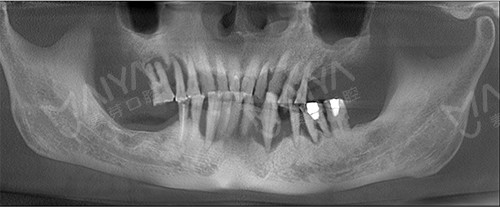

李大爷到院拍完CT和口腔全景片,了解到情况后,麦芽口腔的种植技术院长指出:由于长期对口腔疏于护理,李老的牙周情况非常差,余牙松动,且牙槽骨萎缩、吸收,现存骨量无法进行传统的种植牙术式。

麦芽的院长指出, All-ON-4种植牙技术打破传统种植技术瓶颈,可以破解牙槽骨萎缩、骨量不足等种植难题,而且手术过程无需植骨,让老年缺牙群体也能实现快速种牙。麦芽口腔院长针对李大爷的情况,对ALL-ON-4种植技术进行升级和改造,为其量身定制了"ALL-ON-5"种植方案。